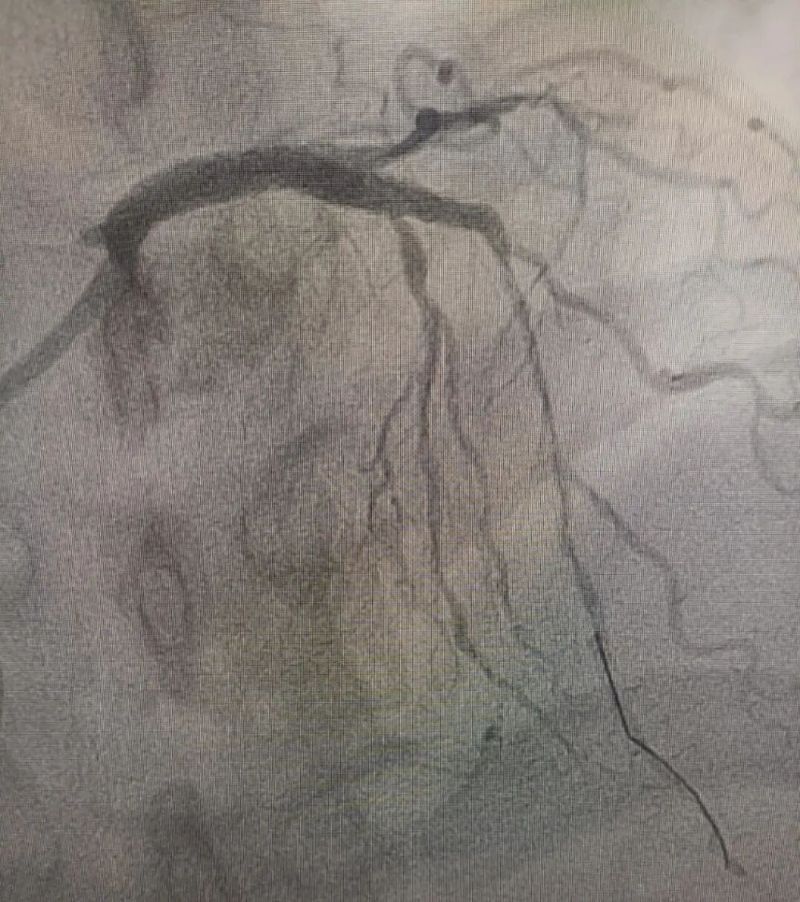

術中造影顯示,左主干至前降支近段重度狹窄——這正是導致心臟缺血、誘發(fā)室顫的“罪魁禍首”。主動脈球囊反搏植入、球囊擴張、支架植入......介入團隊精準操作,一氣呵成。堵塞的血管順利開通,血流重新涌動,這顆一度瀕臨停跳的心臟終于重獲生機。

冠狀動脈造影圖

術后(左主干至前降支近段原狹窄消失)